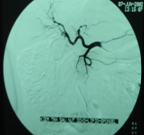

Máy chụp cắt lớp vi tính đa dẫy (MutiSection Computed Tomography- MSCT). Với máy thế hệ mới nhất này, trong một vòng quay của bóng có thể cắt tới 128 lát cắt. MSCT ứng dụng chủ yếu trong thăm khám tim và mạch máu, trong đó có động mạch vành, kiểm tra các bất thường về giải phẫu động mạch vành, các cầu nối mạch vành, thăm dò hoạt động các buồng tim, đánh giá tình trạng vôi hoá động mạch vành, các mạch máu phổi, ngoài ra MSCT giúp đánh giá tình trạng tưới máu cơ tim trong bệnh thiếu máu cơ tim cục bộ. MSCT còn đánh giá bệnh lý động mạch như phình, bóc tách động mạch chủ, động mạch đùi, động mạch chậu rất chính xác. Kiểm tra sau phẫu thuật, sau đặt Stent động mạch cũng nhờ vào MSCT.

Hình hẹp động mạch vành trên MSCT